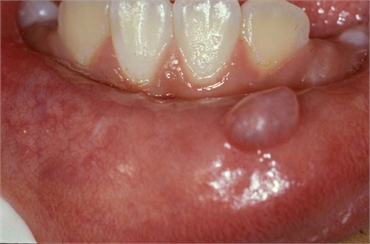

Mucocele mucous cyst

The blockage of salivary ducts causes the saliva to leak into the surrounding soft tissues. This is commonly associated with minor salivary glands and is called extravasation cyst. When this phenomena takes place in major salivary glands, it is called a retention cyst. A mucocele's outer covering is called a pseudocapsule. Since mucocele commonly occurs on smooth surfaces like the lower lips and inner lining of the cheeks (buccal mucosa), the patient tends to bite the lesion, thereby rupture the pseudocapsule and cause repeated injuries at the site. This leads to the recurrence of the mucocele.

A dentist diagnoses a mucocele with proper history taking of the patient. Even though a definitive diagnosis is confirmed only through laboratory investigations, clinical diagnosis can be narrowed down by the patient's medical conditions, site of the mucocele and decoding the cause of the lesion. A mucocele can be firm or fluctuant in its consistency and has a pink or bluish tinge in its color. It rarely measures more than 1.5 cm and is asymptomatic.